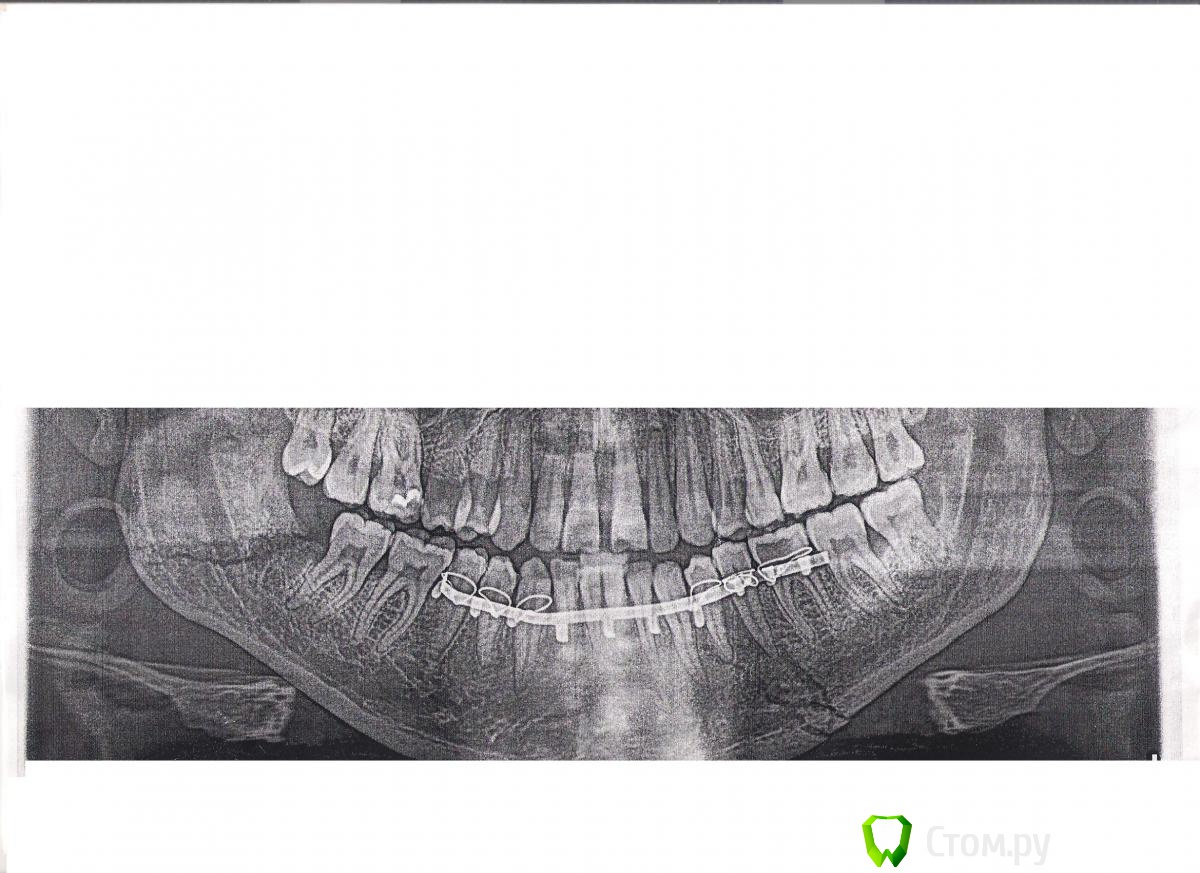

Lucifer08 Опубликовано 27 ноября, 2014 Поделиться Опубликовано 27 ноября, 2014 Здравствуйте, мне 32 годаДвойной перелом челюсти со смещением отломков 29 09 2014, шины поставили 09.10.2014,но резинки снял через 2 недели, ходил только с шинами (по работе надо было выглядеть без резинок).После снятия шин (13.11.14) (сам дома снимал) три зуба (43,44,45) ушли в сторону,шатаются и болят,но жевать не больно.На консультации, челюстно-лицевой хирург сказал, что всё срослось и это пройдет, но зубы, то так встанут, то по другому, и подбородок постоянно немой. Снимок могу переслать , господа доктора, подскажите, что делать?????? Ссылка на комментарий

SDC Опубликовано 27 ноября, 2014 Поделиться Опубликовано 27 ноября, 2014 Здравствуйте, мне 32 годаДвойной перелом челюсти со смещением отломков 29 09 2014, шины поставили 09.10.2014,но резинки снял через 2 недели, ходил только с шинами (по работе надо было выглядеть без резинок).После снятия шин (13.11.14) (сам дома снимал) три зуба (43,44,45) ушли в сторону,шатаются и болят,но жевать не больно.На консультации, челюстно-лицевой хирург сказал, что всё срослось и это пройдет, но зубы, то так встанут, то по другому, и подбородок постоянно немой. Снимок могу переслать , господа доктора, подскажите, что делать??????Давайте снимки смотреть и здорово было бы сделать фото 1 Ссылка на комментарий

Lucifer08 Опубликовано 28 ноября, 2014 Поделиться Опубликовано 28 ноября, 2014 Давайте снимки смотреть и здорово было бы сделать фото Ссылка на комментарий

Lucifer08 Опубликовано 28 ноября, 2014 Поделиться Опубликовано 28 ноября, 2014 Давайте снимки смотреть и здорово было бы сделать фото А вот фото зубов Ссылка на комментарий